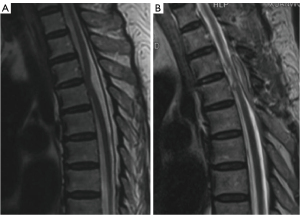

Magnetic resonance imaging (MRI) was used for each patient and showed typical demonstration of widened posterior subarachnoid space and C-shaped ventral deformation of the spinal cord at the affected level (Figure 1A,1B). Computed tomography myelography was used for further differentiation if necessary to reveal dural defects (Figure 1C).

ISCH is a rare cause of spinal cord dysfunction for which the etiology and natural history has remained disputed. Many theories have been reported, including congenital defect, duplication defect, and acquired dural defects caused by herniated discs (20,23,25,26). Diagnosis is often difficult due to poor knowledge of the disease (27). In our case series, the greatest length of time between symptom onset to treatment was over 30 years. When the spinal cord is tethered by the ventral dural defect, CSF pulsation and pressure gradient will slowly exacerbate the injury (28). Reducing the rate of missed diagnosis requires better understanding of the imaging features of the disease. The typical characteristics of ISCH on T2 sequences are C-shaped spinal cord attaching to ventral part of dura, and enlarged dorsal CSF space, mainly in the thoracic region.